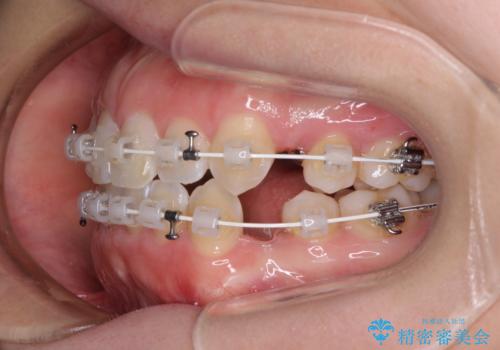

- 矯正装置

- 審美装置

- 治療計画

- 口元の突出感と口の閉じにくさ、前歯のデコボコを気にして来院された患者様です。

上下左右第一小臼歯4本を抜歯し、ワイヤー装置にて口元を引っ込めるよう矯正治療を行うこととしました。

骨格的に下顎骨が前方位にあるため、口元の突出感改善には限界があると思われましたが、唇の閉じにくさが改善するほど引っ込めることができました。